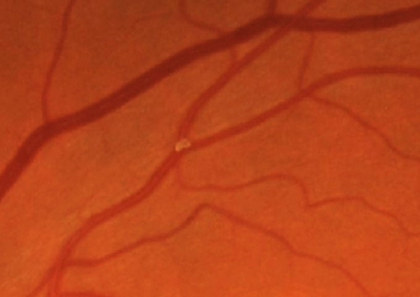

2. Calcific: These emboli typically originate from calcified cardiac valves, particularly in calcific aortic valve stenosis. They are whiter in colour and highly refractile. They are typically associated with occlusion of larger retinal arteries and found closer to the optic disc.